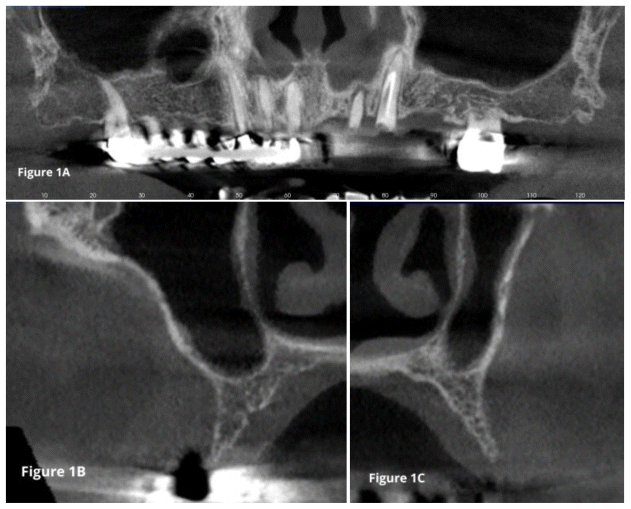

Intraoral examination and panoramic radiographic assessment (Figures 1 and 2) indicated the need for implant-prosthetic rehabilitation treatment.

After analyzing the second-level radiographic examination, specifically the CBCT scan, and in agreement with the patient, it was decided to fulfill his specific request to perform a fixed prosthetic rehabilitation with implant support.

A follow-up CBCT scan was performed two years after surgery. The Schneiderian membrane showed physiological ventilation with no signs of inflammation (Figure 6).

A careful preoperative evaluation of bone density using second-level examinations, such as CBCT, is essential in this type of intervention, as it allows the surgeon to identify the best sites for implant placement and the specific surgical procedure to be used. Bone density, in fact, significantly influences the primary stability of the implants, tissue healing, and the long-term success of implant rehabilitation (29).